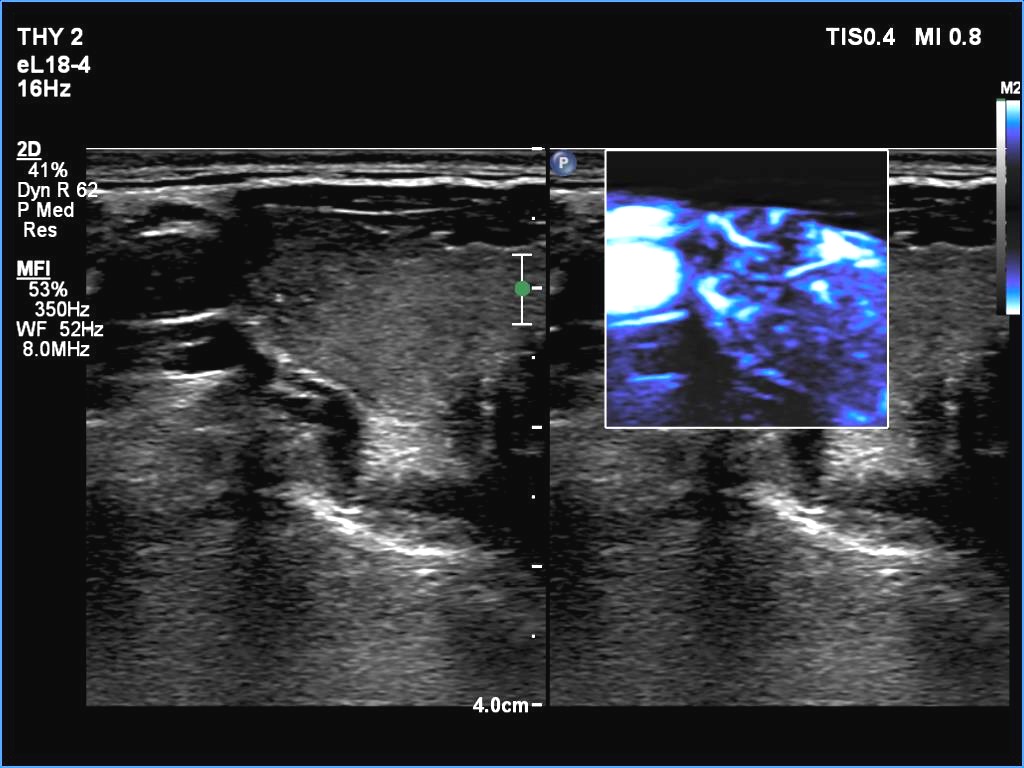

Ultrasonography. The thyroid was echonormal. There were two partly deeply hypoechoic nodules, one in the ventrolateral part of the right lobe and another one in the isthmus. Both had irregular margins and punctate echogenic foci. There was a mirror image artifact of the lesion in the isthmus.

Both nodules had multiple suspicious features: beside deep hypoechogenicity and irregular borders, microcalcifications should be also considered. The nodule in the right lobe presented also three possible sonographic signs of a possible extrathyroidal spread: the pseudocapsule of the thyroid was not intact, the lesion had both abutting and butting contours.